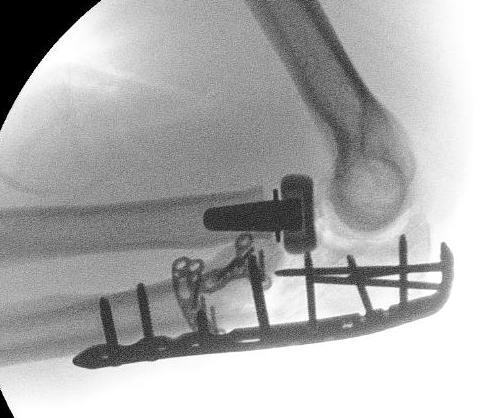

Olecranon plate + ORIF Type II coronoid process + radial head replacement

Olecranon plate with radial head replacement

Olecranon plate with radial head replacement + LCL repair

Olecranon plate + medial coronoid buttress plate + radial head replacement

Complex proximal ulna fracture with radial head replacement subluxation